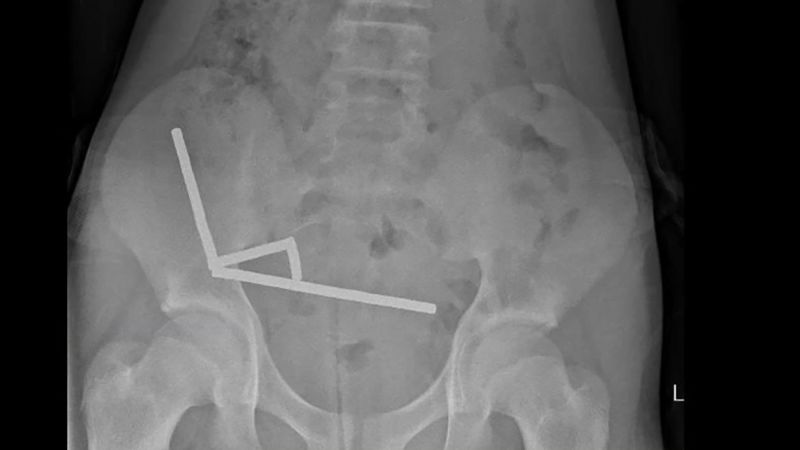

Scans showed that the magnets were clustered in four chains in the lower right part of the abdomen, magnetically drawing different parts of the intestines together, the report said, noting that some images were distorted by the magnets. Doctors then proceeded with an exploratory surgery.